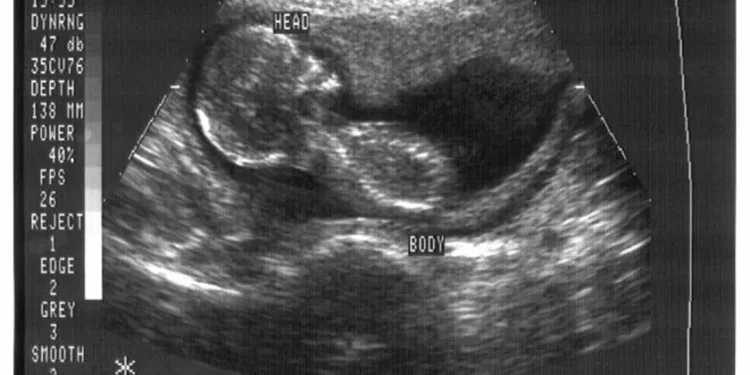

Nos últimos anos, a ciência tem avançado de forma surpreendente, trazendo soluções para problemas que antes pareciam impossíveis de serem resolvidos. Um desses avanços é a possibilidade de tratar a infertilidade em mulheres que não conseguem mais produzir ovócitos, criando-os a partir de outras células. Essa é uma ideia que, até pouco tempo atrás, parecia pertencer apenas à ficção científica, mas que agora está se tornando uma realidade cada vez mais próxima.

A infertilidade é um problema que afeta milhões de casais em todo o mundo. Segundo a Organização Mundial da Saúde (OMS), cerca de 15% da população mundial em idade reprodutiva sofre com algum tipo de infertilidade. Entre as mulheres, a principal causa é a falência ovariana precoce, que é quando os ovários param de funcionar antes dos 40 anos de idade. Isso pode acontecer por diversos motivos, como doenças genéticas, tratamentos de câncer, uso de drogas ou simplesmente por questões genéticas.

Até agora, a única opção para essas mulheres era recorrer à doação de óvulos, o que muitas vezes é um processo caro e complexo. Além disso, nem sempre é possível encontrar uma doadora compatível e o tempo de espera pode ser longo. Por isso, a possibilidade de criar ovócitos a partir de outras células é um avanço revolucionário que pode mudar a vida de muitas mulheres que desejam ser mães.

Mas como isso é possível? A técnica utilizada é chamada de “reprogramação celular”, que consiste em transformar células adultas em células-tronco pluripotentes, ou seja, células que podem se diferenciar em qualquer tipo de célula do corpo. Essas células-tronco são então estimuladas a se transformarem em células germinativas, que são as precursoras dos óvulos. Essa técnica já foi testada com sucesso em camundongos e agora está sendo aplicada em seres humanos.

Um dos principais desafios dessa técnica é garantir que os ovócitos criados sejam de qualidade e possam ser fertilizados. Para isso, os pesquisadores estão trabalhando em aprimorar a técnica e garantir que os ovócitos produzidos sejam saudáveis e viáveis para a fertilização. Além disso, também é necessário garantir que esses ovócitos não apresentem nenhum tipo de alteração genética que possa ser transmitida para os futuros filhos.

Outro ponto importante é que essa técnica pode ser uma alternativa para mulheres que desejam preservar sua fertilidade, seja por motivos médicos ou pessoais. Atualmente, a criopreservação de óvulos é a única opção para isso, mas nem sempre é viável para todas as mulheres. Com a possibilidade de criar ovócitos a partir de outras células, essa opção se torna mais acessível e pode ser uma solução para muitas mulheres que desejam adiar a maternidade.

É importante ressaltar que essa técnica ainda está em fase de pesquisa e testes, mas os resultados até agora são promissores. Além disso, é necessário que haja uma regulamentação ética e legal para o uso dessa técnica, garantindo que ela seja utilizada de forma responsável e segura. Mas é inegável que essa é uma grande conquista da ciência e que pode trazer esperança para muitas mulheres que desejam ser mães.